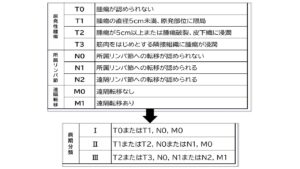

血管肉腫のステージ分類

血管肉腫はリンパ節への転移、肺など他の臓器への遠隔転移の有無などでステージ分類されます。

血管肉腫の予後は非常に良くないと言われています。脾臓にできる血管肉腫の生存期間の中央値は、無治療の場合で約1ヶ月、脾臓摘出をした場合で約3ヵ月、脾臓摘出後に化学療法をした場合で6ヵ月、脾臓摘出後に化学療法と免疫賦活薬を併用した場合で9ヵ月が一つの目安になります。

脾臓以外の部位に発生する血管肉腫については、真皮血管肉腫(真皮下への浸潤なし)の外科切除での生存期間中央値は約26か月、皮下織や筋肉の血管肉腫の生存期間中央値は約5ヶ月、皮下織・筋肉への浸潤がある場合の生存期間中央値は約10ヶ月と報告されています。

心臓にできる血管肉腫は脾臓よりもさらに予後が悪いと言われてり、外科的に切除できたとしても1~4ヶ月程度と言われています。